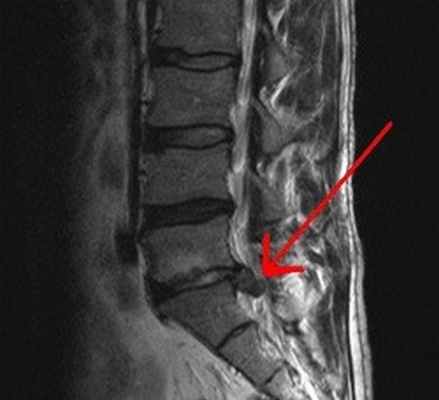

Как выглядит грыжа на МРТ

| МРТ снимок - грыжа поясничного отдела позвоночника | МРТ снимок - грыжа шейного отдела позвоночника | МРТ снимок - грыжа грудного отдела позвоночника |

![]() | ![]() | ![]() |

По причине более высокой нагрузки самыми частыми местами образования грыж являются позвонки L4 - L5 в области поясницы и L5 - S1. В ходе МРТ на сагиттальном срезе позвоночника при грыже врач-рентгенолог будет видеть четкое выбухание межпозвонкового диска. Будет видно, как часть пульпозного ядра из-за разрыва кольца вышла в спинномозговой канал. На МРТ-фото врачи смогут увидеть размеры грыжи, расположение, в какую сторону происходит выпячивание и степень давления на окружающие ткани.